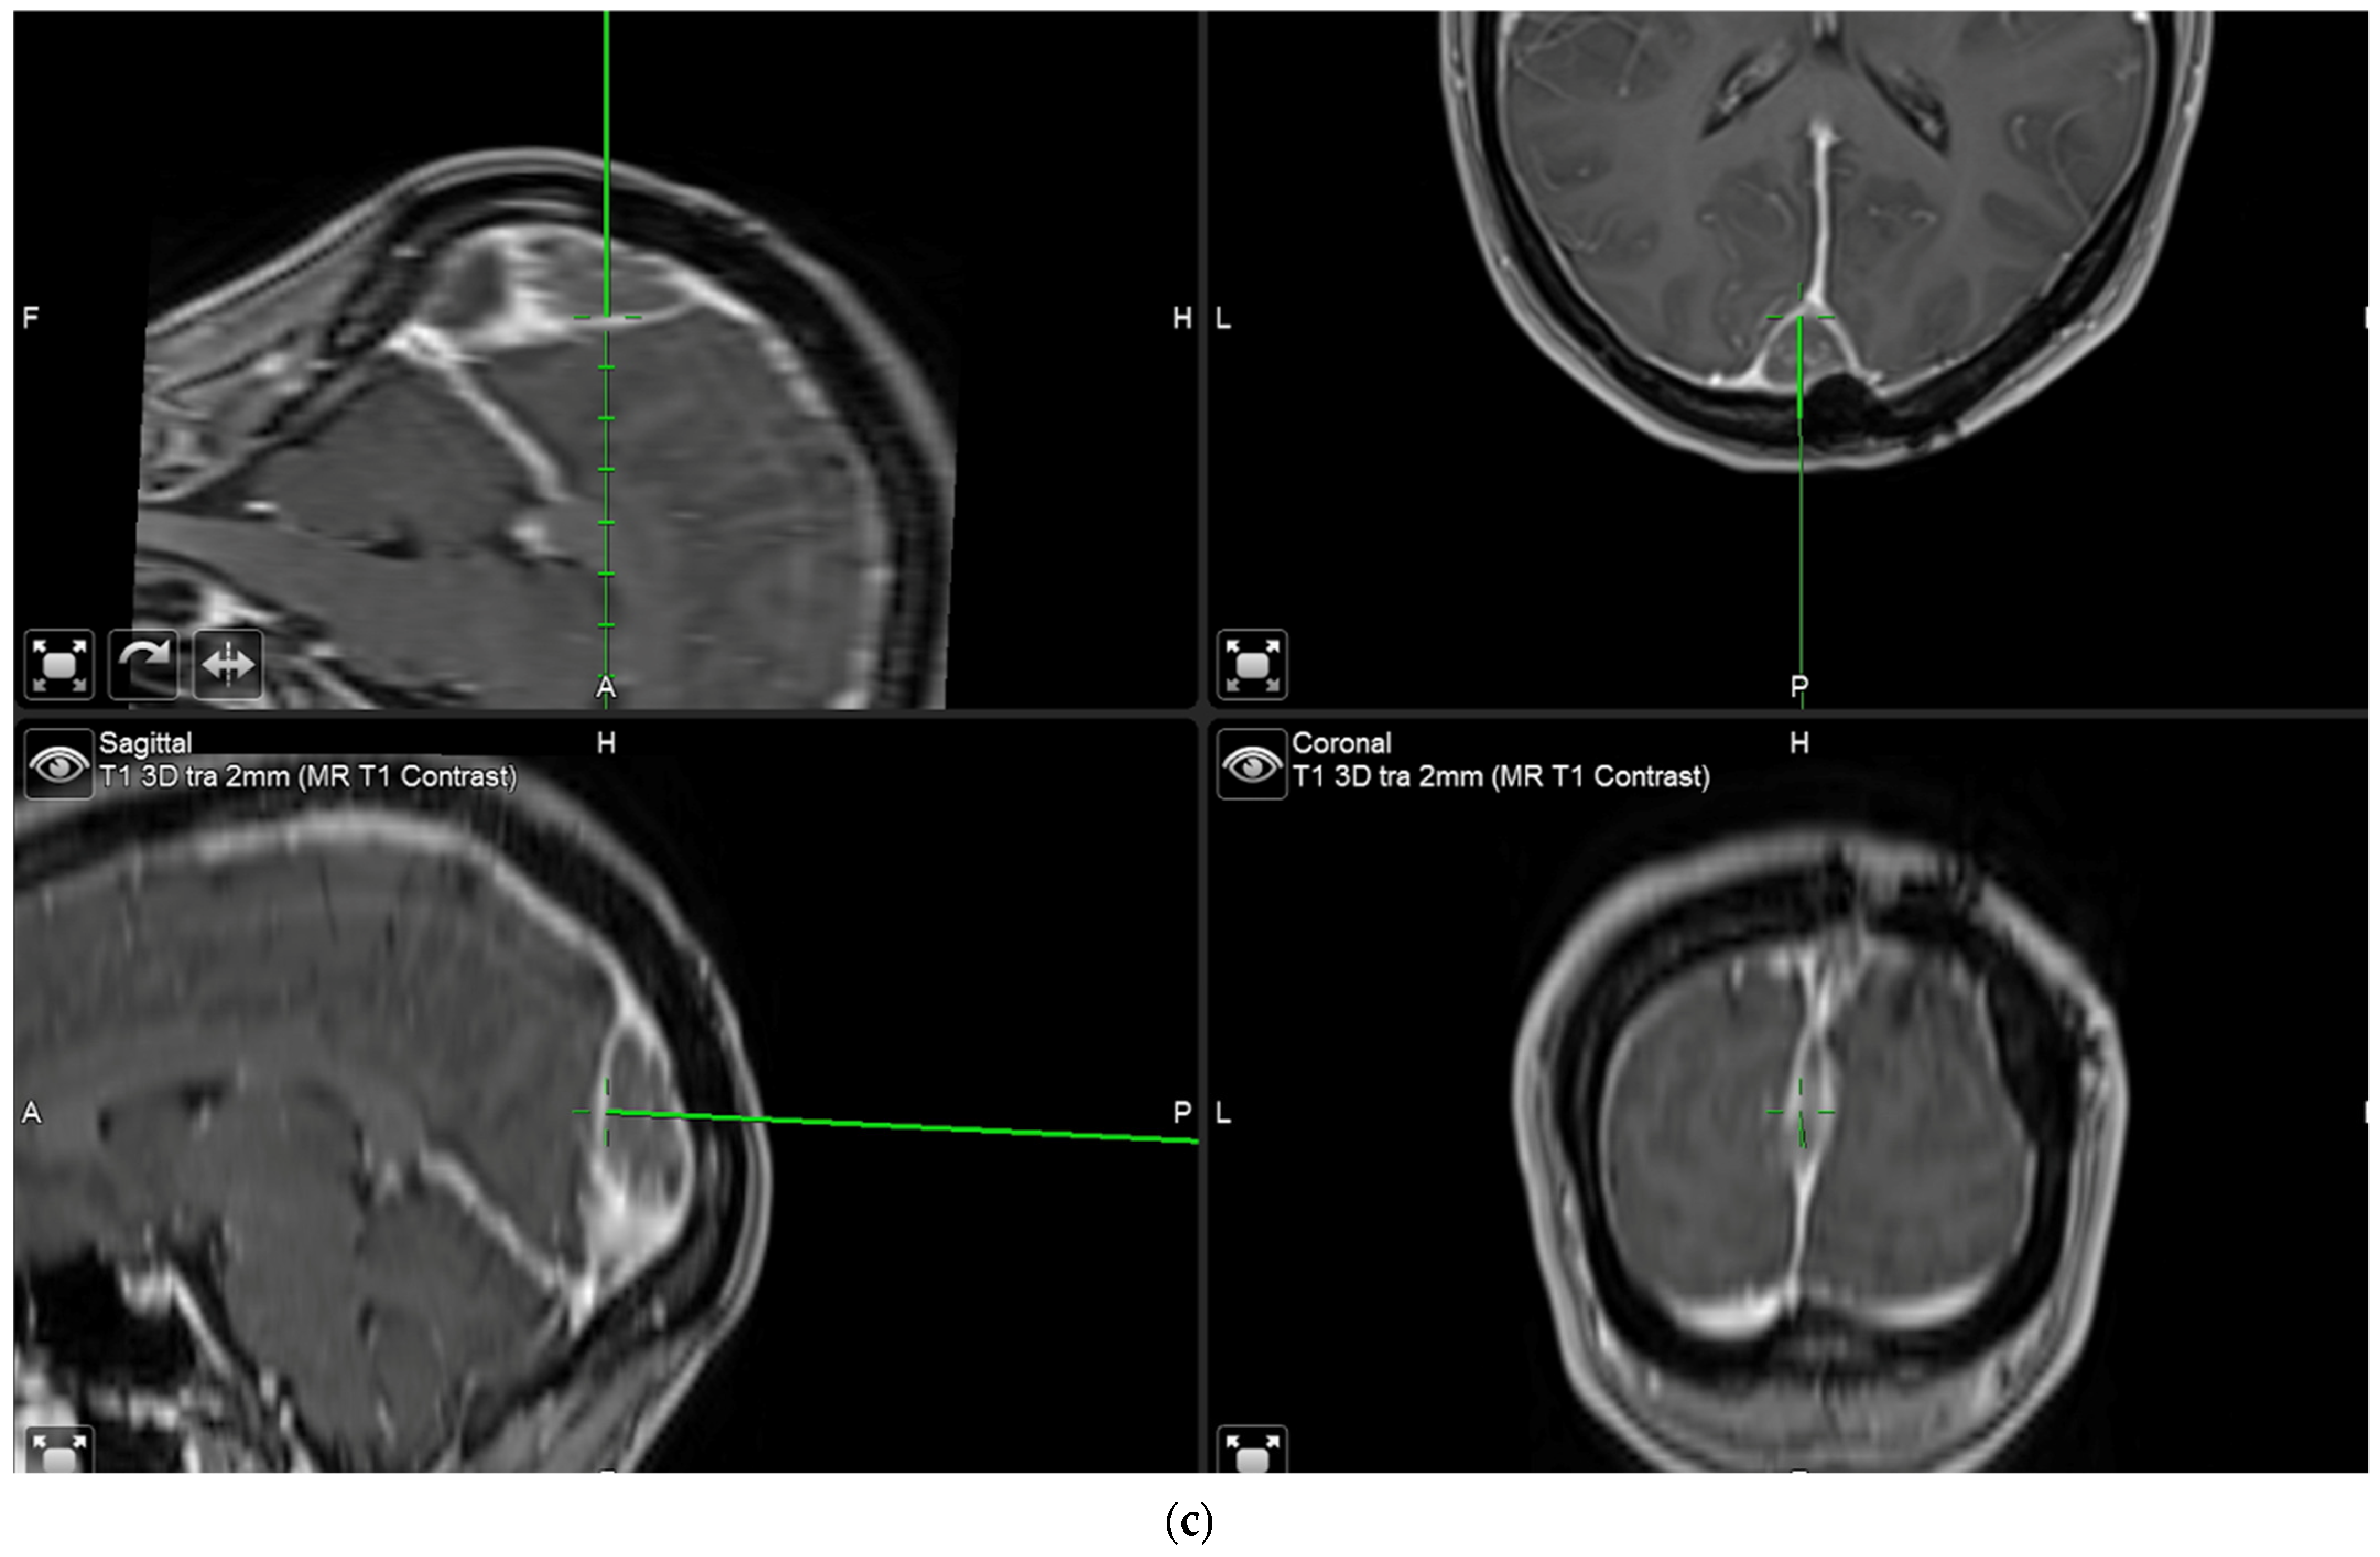

The aim of fluorescence assessment and tissue biopsy in bulk tumor is to determine whether a tumor shows fluorescence and to correlate fluorescence with tumor histology. To collect this biopsy, surgeons are asked to switch to blue light as soon as bulk tumor is encountered during surgery, to determine whether any fluorescence is visible and to take a biopsy from a fluorescing part of the tumor. A neuronavigation screenshot is taken from the exact location of the biopsy (Figure 1). The entire sequence is recorded using the microscope’s video system.

Biopsy acquisition from bulk tumor. As soon as surgeons encounter bulk tumor during surgery, they change to blue light, determine whether any fluorescence is visible, and, if so, take a biopsy from fluorescing tissue after taking a neuronavigation screenshot. The biopsy procedure is recorded for later assessment by the review panel. (a) Brain with visible bulk meningioma under elevated dura in a patient with tumor in the superior sagittal sinus infiltrating the adjacent brain. Insert shows pointer tip location marking the intended biopsy location. (b) Strong fluorescence of tumor under blue light, which is biopsied. (c) Neuronavigation screenshot (“F”: footwards; “H”: headward; “A”: anterior; “P”: posterior; “L”: left).